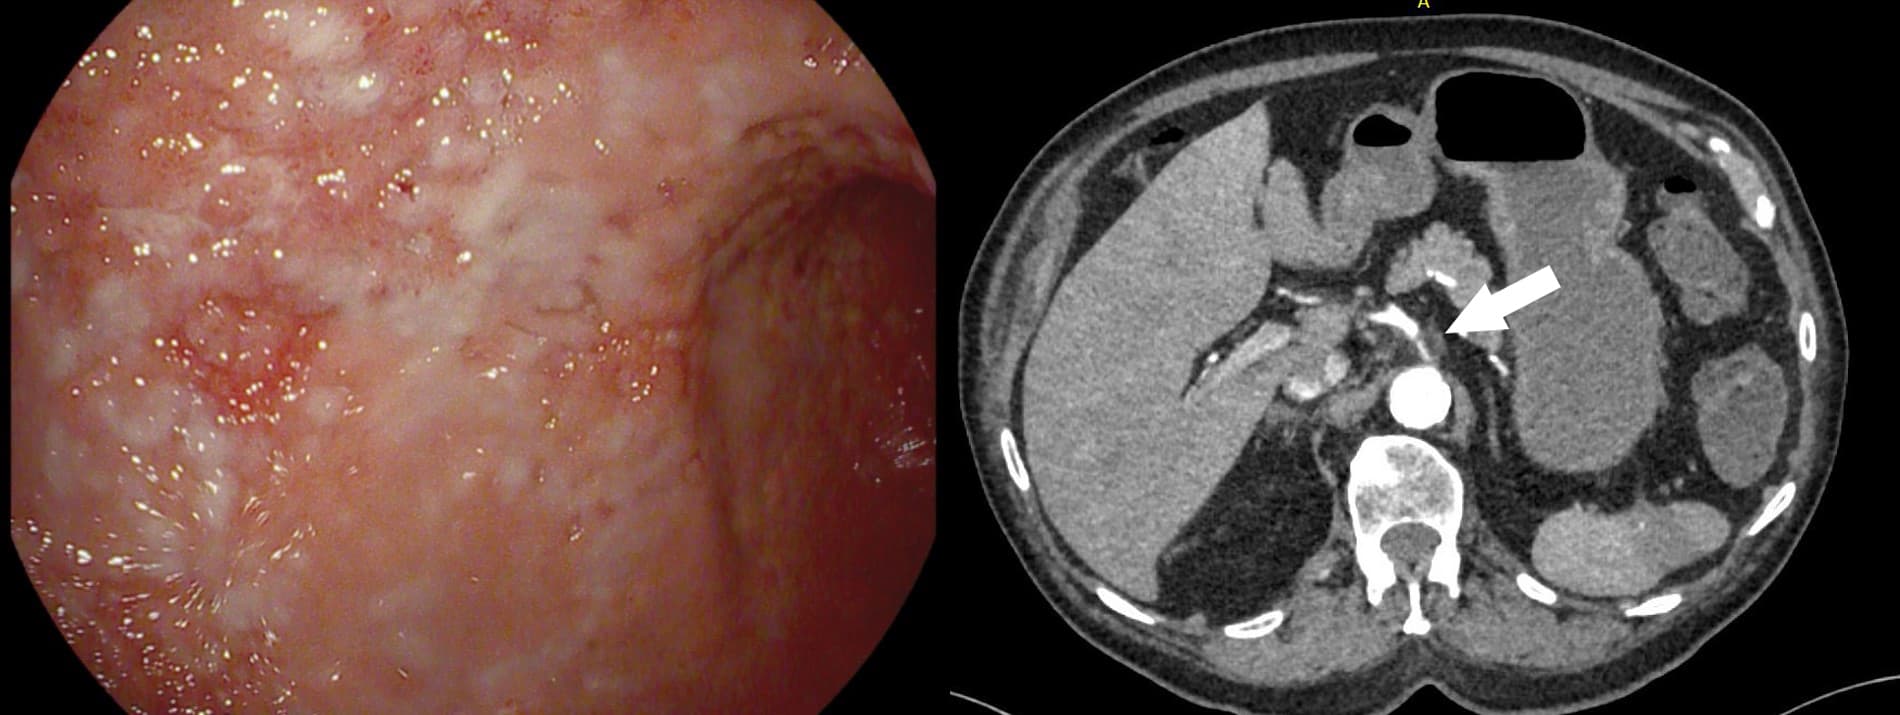

En 83-årig mand med claudicatio intermittens og stent i arteria iliacae blev indlagt med diffuse abdominalsmerter og natlige opkastninger gennem flere døgn. Ved gastroskopi genfandt man kroniske ventrikelulcerationer, der var kendt fra tidligere gastroskopier, men også bleghed og atrofi af slimhinden.

På mistanke om mesenteriel iskæmi blev der foretaget en akut CT-angiografi af abdomen, hvor man så udtalt arteriosklerose i aorta abdominalis med gracilt trådfin fyldning af truncus coeliacus (TC). En subakut aortagrafi viste total okklusion af TC og moderat stenose af a. mesenterica superior (SMA), hvorfor det kun var muligt at anlægge stent i SMA, hvilket desværre ikke fuldstændigt afhjalp patientens symptomer.